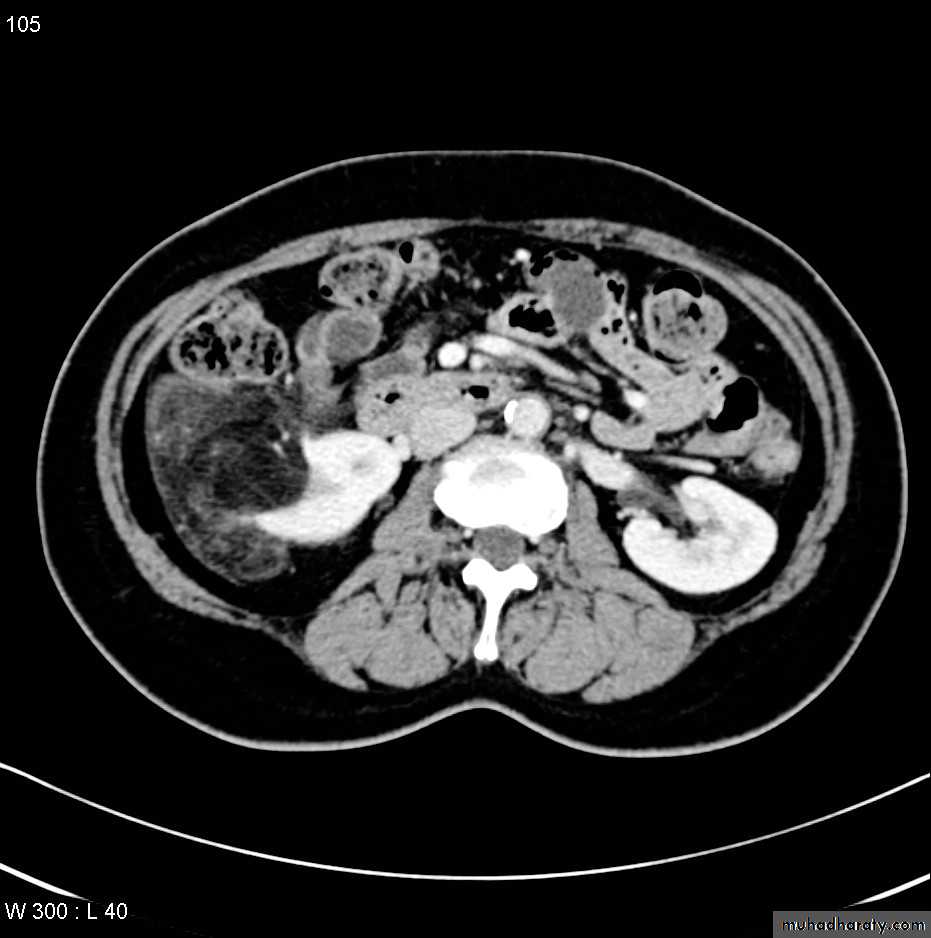

CT scanContrast enhanced CT scan through the kidneys in nephrogram phase 90-100 seconds following contrast administration and would show renal lesions well.

RENAL CELL CARCINOMA(RCC)

Most common malignant renal masses.Spherical or lobulated similar density to the adjacent renal cortex.

May have areas of necrosis.

Enhances heterogeneously and less than that of the adjacent renal parenchyma.

CT is sufficiently accurate so that preoperative biopsy is rarely performed.

Staging is best by CT except for vascular invasion where MRI will be superior.

Staging parameters include : local direct spread, retroperitoneal L.Ns enlargement, liver adrenal or pancreatic metastasis and renal vein or IVC involvement.